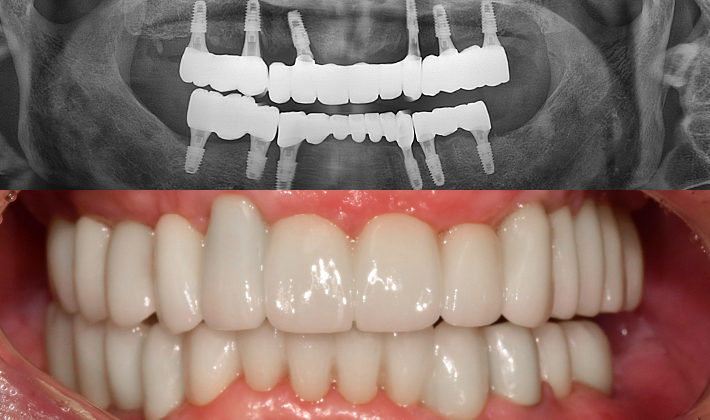

치과가 무서워 10년 동안 미뤄온 임플란트 수술 그 결과는?

2026.01.21